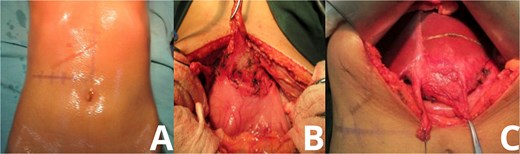

Upon entering the peritoneal cavity, dense adhesions were noted between the round ligament and the lesser curvature of the stomach. Careful dissection revealed a well-encapsulated mass located in hepatic segment 3. The mass was tightly adhered to surrounding structures but was eventually mobilized without injury to adjacent organs. The liver parenchyma was marked, and a formal anatomical resection of segment 3 was performed (Fig. 2).

Intraoperative exposure of intrahepatic gossypiboma. Photographs taken during exploratory laparotomy document the identification and mobilization of the gossypiboma. (A) Initial intra-abdominal view reveals dense adhesions between the round ligament and lesser curvature of the stomach. (B, C) Progressive dissection exposes a fibrous, well-encapsulated mass within hepatic segment 3. The mass is separated from surrounding structures with careful technique, avoiding injury to adjacent organs.